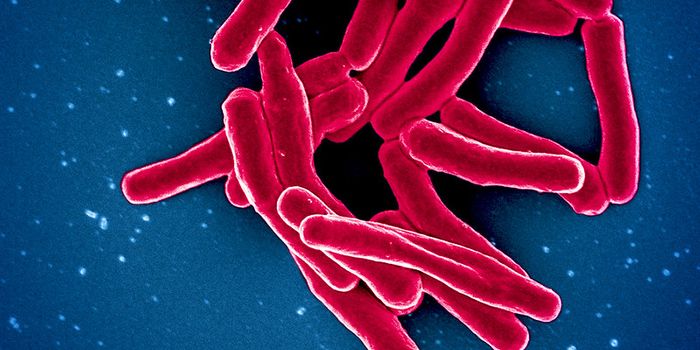

JAN 22, 2020Clinical & Molecular DXWhat if there was a test that could detect tuberculosis six months before symptoms appear? Researchers at the University ...